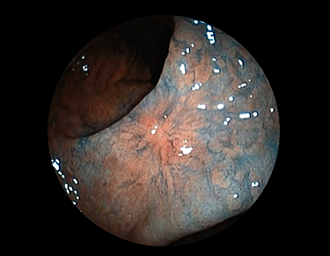

症例3:十二指腸潰瘍(53才男性)

1年前からの慢性胃痛を主訴に当院受診。十二指腸球部前壁に深くて大きな潰瘍(Stage A1)があり、潰瘍底は厚い白苔に覆われ、一部白苔のはみ出しを認める。潰瘍周囲粘膜は浮腫を伴っている。ボノプラザンフマル酸塩投薬で治療開始しました。

通常画像